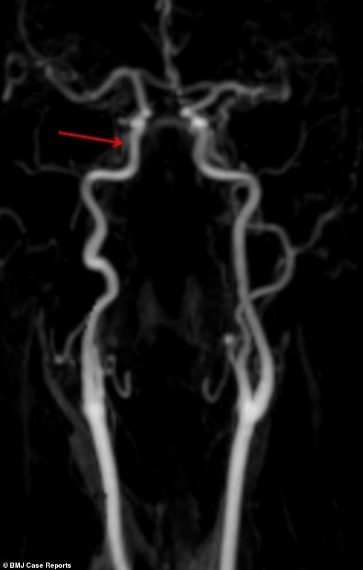

La scansione cerebrale mostra l'arteria guarita

• La scansione cerebrale mostra l'arteria ispessita e quindi indebolita

• La lunghezza dell'arteria che si è rotta durante l'incidente

Travolta da un'onda, donna avverte mal di testa: la radiografia mostra i gravi danni subiti

Dopo essere stata travolta da un'onda in vacanza, per una turista irlandese sono iniziati seri problemi. La donna, 60 anni, ha iniziato a soffrire di mal di testa e dolori al collo, oltre che fastidi alle palpebre e alle pupille. Le scansioni cerebrali hanno mostrato che l'urto dell'onda aveva provocato la rottura di vasi sanguigni e di un'arteria nel collo che porta sangue al cervello. I medici, sbalorditi, hanno pubblicato il racconto in una rivista medica e dichiarando che si trattava del primo caso di questo genere. Alla paziente è stata diagnosticata la rara condizione della sindrome di Horner, secondo il racconto pubblicato su BMJ Case Reports. Una condizione causata da danni ai nervi del viso e risultati nella bulbo oculare che affonda nella sua cavità. All'ospedale della Galway University, i medici hanno scoperto che gli occhi della paziente si muovevano involontariamente, ma era comunque in buona salute. Dopo aver assunto inizialmente l'aspirina per evitare l'ictus, la paziente è pienamente guarita sei mesi dopo.